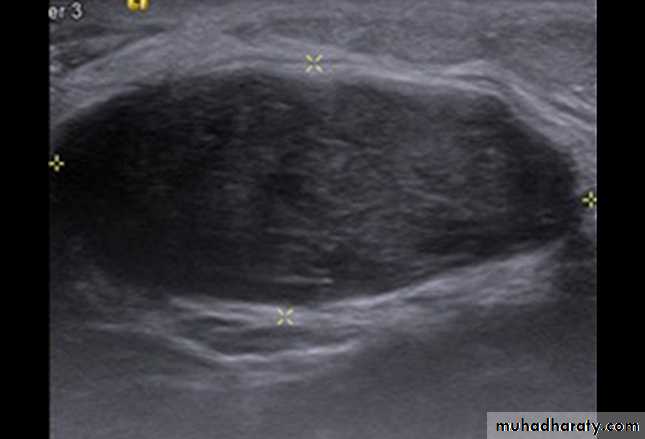

US characteristics of benign breast mass

1.well circumscribed, hyperechoic tissue2.wider than deep

3.gently curving smooth lobulations (<3 in no.)

4.thin echogenic pseudocapsule

5.sonographic posterior acoustic enhancement

6.homogeneous echotexture

7.compressible

8.normal/poor vascularity ( by Doppler )

9. no associated axially LNP